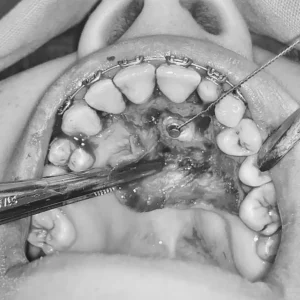

Retención dental

Expresión frecuente: «Me duelen las muelas del juicio»

El tercer molar es el diente impactado con mayor frecuencia, sin embargo cualquier otro diente puede estarlo; hallazgo común entre adolescentes y en adultos jóvenes.

Minimizar los riesgos derivados de la extracción o cirugía de retención de dientes impactados y gestionar eficazmente las complicaciones cuando se presentan son funciones fundamentales del cirujano oral y maxilofacial en la práctica clínica actual.

Los dientes retenidos o incluidos (atrapados) no siempre se retiran, también a través de cirugía y ortodoncia se pueden reposicionar.